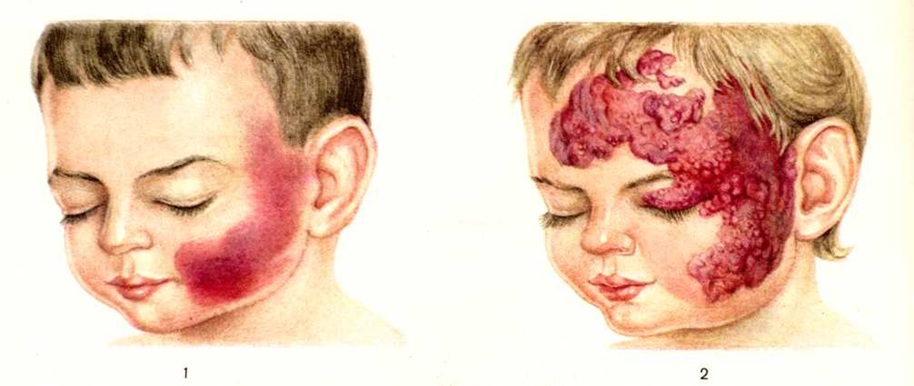

ГемангиомаГемангиома (haemangioma; греческий haima кровь + angeion сосуд + -oma) — доброкачественная опухоль, развивающаяся из кровеносных сосудов. Гемангиома возникает на основе врождённого порока развития сосудов и выявляется обычно с момента рождения ребёнка. По сообщению Пака и Эриэла (G. Т. Pack, I. М. Ariel), на Гемангиома (у взрослых) приходится 22% среди всех доброкачественных опухолей и 46% среди всех опухолей мягких тканей. Патологическая анатомияВ формировании Гемангиома принимают участие почти все элементы стенки сосуда, но располагаются они атипично и иногда преобладают некоторые составные части стенки. По морфологически строению различают несколько разновидностей Гемангиома. Капиллярная (гипертрофическая), или простая, Гемангиома состоит из большого количества переплетающихся капилляров со стенкой из набухшего эндотелия, образующего как бы несколько слоёв. Ряд капилляров опухоли находится в спавшемся состоянии, эндотелий их расположен в виде концентрических групп и вытянутых тяжей. Капиллярные Гемангиома нередко отличаются инфильтрирующим ростом, оставаясь вполне доброкачественными опухолями. Кавернозная (пещеристая) Гемангиома представлена крупными полостями раз личной формы, наполненными кровью, выстланными эндотелием и разграниченными тонкими перегородками из соединительной ткани. Иногда кровь в полостях свёртывается и образовавшаяся тромботическая масса организуется. Случаев малигнизации Гемангиома не наблюдается. Системные опухолевидные разрастания сосудов (артериального, венозного и капиллярного типа) с образованием кавернозных полостей и сосудистых тяжей называются ангиоматозом или гемангиоматозом. Поражается чаще всего целая конечность или её дистальный отдел. Клиническое течение гемангиоматоза и методы его лечения не отличаются от солитарной Гемангиома. Встречаются пороки развития лимфатических и кровеносных сосудов одновременно. Новообразования подобного типа называют гемолимфангиомой. Клиническая картина определяется локализацией Гемангиома. Встречаются Гемангиома различной локализации: кожи с подкожной клетчаткой и слизистых оболочек; мышц, сухожилий и костей; паренхиматозных органов. Наиболее распространённой формой является Гемангиома кожных покровов и слизистых оболочек. Особенно часто поражается кожа лица и шеи. На эту область приходится около 60% всех Гемангиома. Гемангиома кожи развивается преимущественно на лице, встречается в области волосистой части головы, реже на туловище и конечностях. Обычно обнаруживается при рождении или в раннем детском возрасте; увеличивается по мере роста организма. Опухоль может достигать значительных размеров и захватывать большую часть лица, приводя к косметическим и функциональным недостаткам. Встречается несколько разновидностей Гемангиома. Капиллярная Гемангиома кожи (пятнистая, простая, плоская) — пятно пурпурного, розового или синюшно-багрового цвета (цветной рисунок 1), бледнеющее при надавливании; в ряде случаев имеет гладкую поверхность, иногда выступает над уровнем кожи. Нередко пятно со стоит из центрально расположенной точки, от которой радиально расходятся мелкие расширенные сосуды (звездчатая Гемангиома). Разновидностью капиллярной Гемангиома кожи является ангиокератома (смотри). Кавернозная Гемангиома кожи и подкожной клетчатки — отграниченное образование, цвет которого варьирует от вишнёвого до фиолетового (цветной рисунок 2), покрыто неизменённой кожей; размеры образования от булавочной головки до мужского кулака и больше. Образование мягкой консистенции, с гладкой, чаще бугристой поверхностью; при надавливании легко спадается и бледнеет, при сильном кашле или крике может увеличиваться и напрягаться. В ряде случаев кавернозная Гемангиома развивается из плоской Гемангиома. Кавернозная Гемангиома кожи иногда самопроизвольно исчезает. Встречаются множественные кавернозные Гемангиома, рассеянные по коже и внутренним органам. |

Рис. 1. Капиллярная гемангиома. | ||